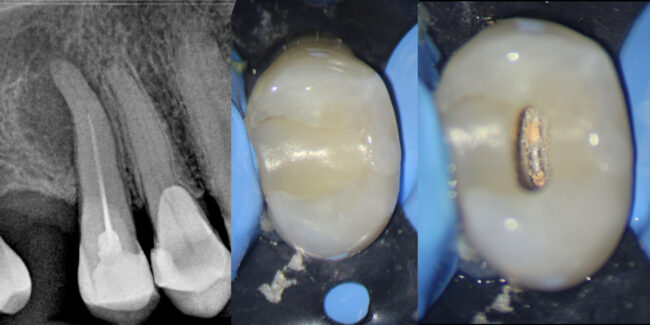

El doctor Noé Hernández nos presenta en este caso clínico una apertura de tipo conservador en un diente 46 en el que se aprecia una gran necrosis pulpar.